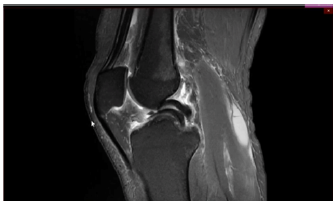

Um paciente de 19 anos de idade sofreu entorse do joelho direito durante agachamento em partida de futebol. Foi retirado do campo e queixando-se de dor na face interna do joelho. Foi levado ao hospital mais próximo e, ao ser examinado, percebeu que não conseguia estender completamente o joelho. Não conseguia flexionar totalmente o joelho também. Notaram-se ainda, edema e o sinal da tecla.

Considere que, no caso clínico descrito, foi realizado o exame complementar, conforme apresentado. Essa figura mostra